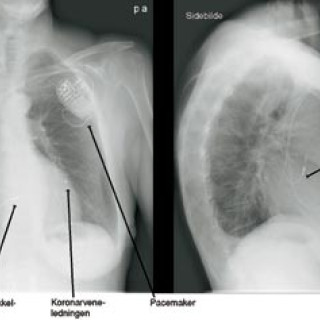

Bildediagnostikk spiller en stor rolle i mange kliniske disipliner, så også i kardiologien. Røntgen thorax, ekkokardiografi med doppler, nukleærmedisinske metoder, invasiv kateterbasert angiografi, MR (magnetisk resonanstomografi, magnettomografi) og i den siste tid også multidetektor-CT er alle metoder som spiller viktige, men ulike roller innen diagnostikk av hjertesykdommer. Metodene har sine sterke og svake sider, dels på grunn av apparaturens tekniske muligheter, dels på grunn av pris, kompetanse og tilgjengelighet. Hensikten med denne artikkelen er å plassere MR i kardiologiens...